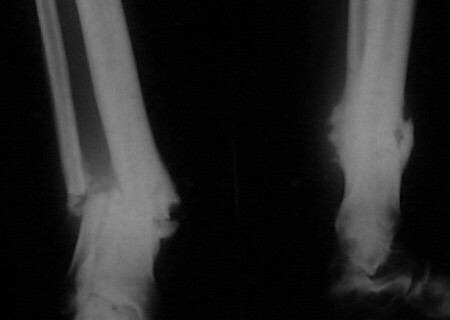

Female. 65 years old. 2 years ago trimalleolar fracture left ankle. First ORIF failed. Second ORIF with autologous graft at the fibular fracture was complicated by infection. The X-ray pictures show the actual situation. What are the suggestions of the group?

Tough case. I would think about the Ilizarov with either closed ankle distraction or with oblique perQ osteotomy through the distal tibia and the talus.

It seem a stiff pseudarthrosis. I will do a axial correction and lengthening if necessary with Ilizarov frame without any corticotomy. Probability of success will be 100% and relapse of infection 0%. You can see one case attached.

In this case, in my opinion, it is necessary to make debridement with economic refreshing of bones from lateral approach with or without correction of deformity on an operational table (the second is more preferable for me because don't short the leg). Make arthrodesis of ankle by Ilizarov technique.